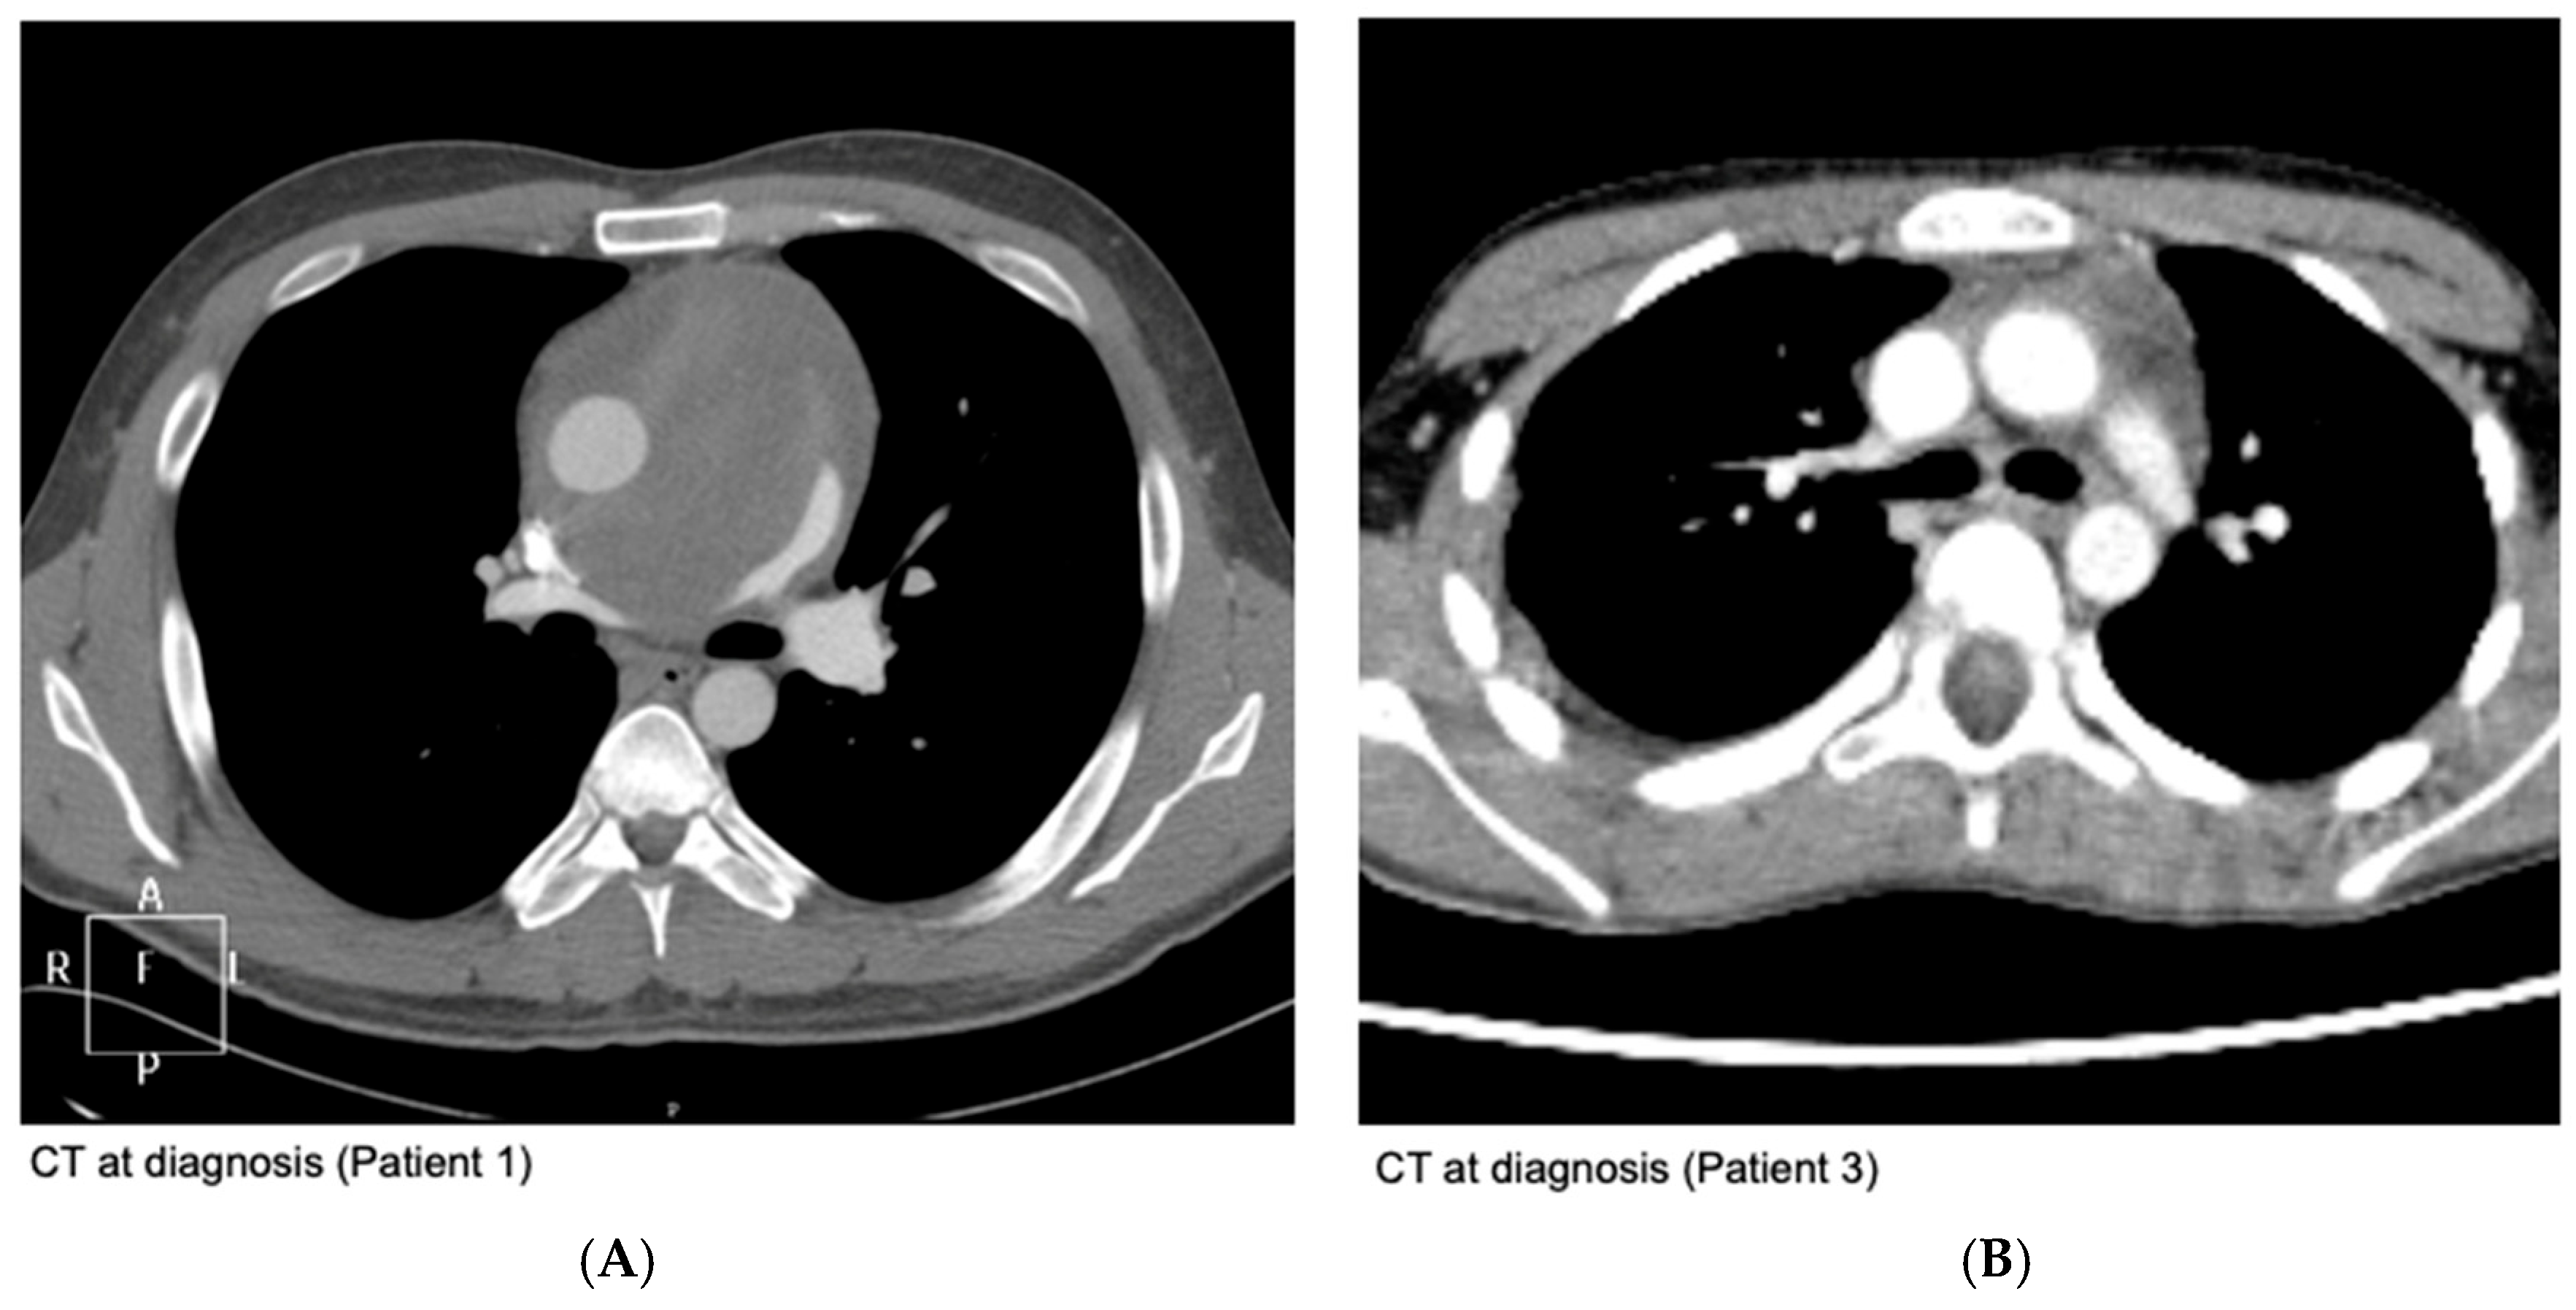

| 1 | 2006 | EE99 | 30 | 11 | Middle | - | VIDE + RTX + VAI | - | 54 | 7.0 |

| 3 | 2007 | EE99 | 11 | 6 | Anterior | - | Surgery + VIDE + VAI + RTX | VATS tumor resection (R1) | 30 | 9.6+ |